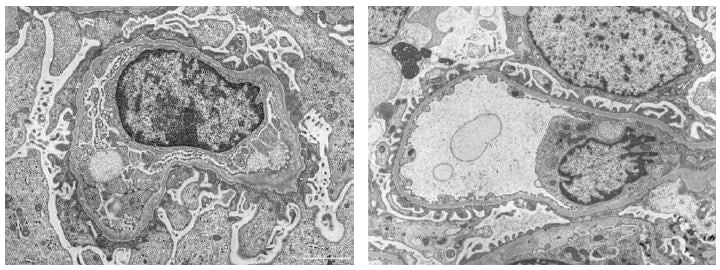

肾穿刺标本的TEM图像

左:Alport综合症、右:薄基底膜肾病

为对比图像的差异性,特为您展示这两种肾病的TEM图像。

稻贺教授指出“低真空SEM和传统TEM、光学显微镜主要的区别是:它可以实现立体观察和三维成像。”“Alport综合症是在基底膜形成网状结构,之前我们一直采用TEM观察切片的二维图像来判断是否发生病变,如篮状细胞的观察,现在我们可以使用低真空SEM观察它真实的三维结构。”

Alport综合症为遗传性疾病,其主要特征是肾小球基底膜发生病变。薄基底膜肾病也是由于肾小球基底膜发生病变引起的,Alport综合症患者往往在青壮年时期发展至终末期肾脏病,必须通过透析进行治疗。这两种肾病的鉴定对于患者的治疗和预后等具有十分重要的意义。冈田教授提到,“过去我们利用免疫染色或透射电子显微镜进行肾病鉴定,现如今诊断技术已实现遗传基因检测,尽管如此,还是不能诊断出肾病类型,而低真空SEM可全面获取标本数据,快速且准确诊断肾病”。